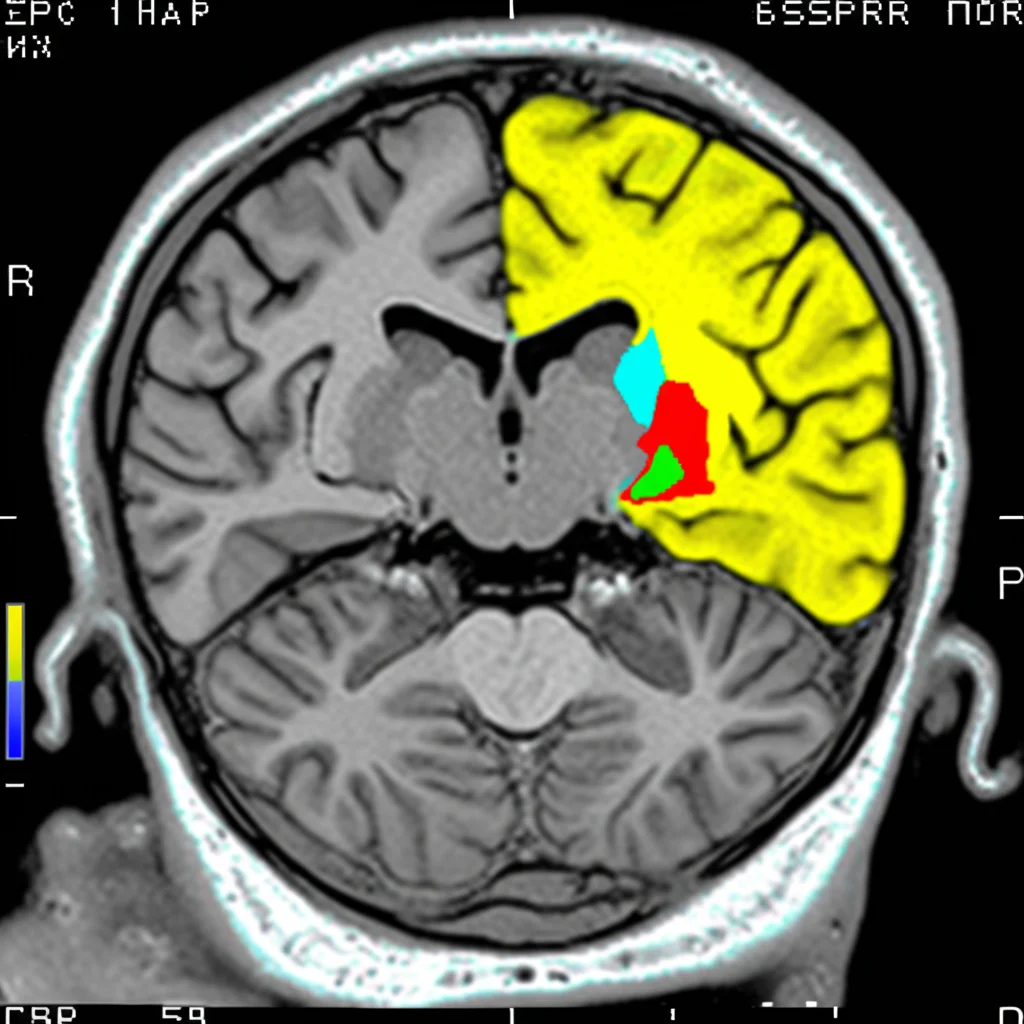

La Risonanza Magnetica: Una Finestra sul Cervello che Cambia

Come facciamo a “vedere” queste differenze nel cervello? Uno strumento potentissimo è la risonanza magnetica (MRI). Ci permette di misurare il volume delle diverse aree cerebrali e identificare i pattern di atrofia. Nel nostro studio, abbiamo utilizzato dati MRI post-mortem (e anche ante-mortem, quando disponibili) di persone con diagnosi di Alzheimer (sia tipico che atipico) e li abbiamo confrontati con cervelli di controllo sani.

Cosa abbiamo scoperto? Beh, come ci si poteva aspettare, entrambi i gruppi di pazienti con Alzheimer mostravano una riduzione di volume rispetto ai controlli, soprattutto nelle aree temporo-occipitali. L’Alzheimer tipico, però, mostrava un’atrofia aggiuntiva nel lobo parietale. Una differenza interessante è emersa nel cingolato posteriore: il suo volume era significativamente più basso nei pazienti con Alzheimer tipico rispetto a quelli con forme atipiche. Questa regione è un hub cruciale per la memoria e diverse reti cerebrali, quindi la sua maggiore sofferenza nel fenotipo tipico potrebbe spiegare in parte la predominanza dei disturbi di memoria.

Tuttavia, non abbiamo trovato quelle differenze nette nei pattern di atrofia che a volte vengono descritte in letteratura (ad esempio, atrofia frontale più marcata nelle forme atipiche). Una possibile spiegazione è che i cervelli che abbiamo analizzato appartenevano a persone in uno stadio avanzato della malattia, dove l’atrofia tende a diventare più diffusa, mascherando le differenze regionali iniziali.